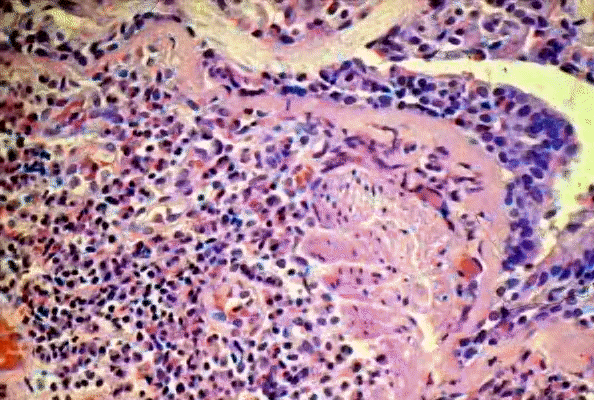

• "Bronchial asthma, higher power. Notice inflammatory cells composed of lymphocytes and many eosinophils. There is prominent thickening of the basement membrane. "

• Ó 1999 KUMC Pathology and the University of Kansas, used with permission; courtesy of Dr. James Fishback, Department of Pathology, University of Kansas Medical Center.